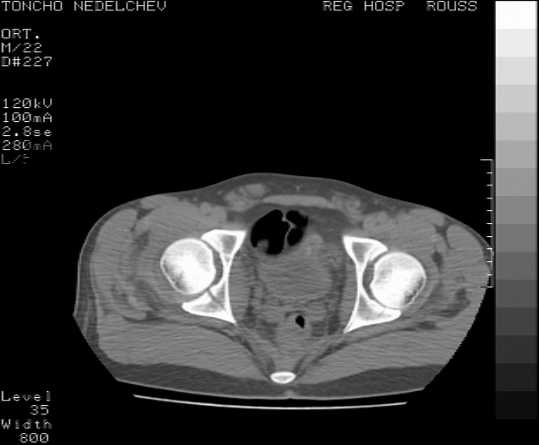

The details of the fracture are not so clear from the images sent...would you be able to send along an AP and Judet images as well as some additional axial images above and below the joint?

I’m not so sure that your patient has a Tr+PW pattern based on the images sent...maybe the fracture’s exact name won’t matter in the long run, but it’d be great to see enough images to make an accurate comment.

Without complete CT images and/or oblique radiographs, it's difficult to answer your question definitively, but it appears that there may not be a posterior wall fracture that requires a posterior approach. A successful reduction through an ilio-inguinal approach will have a faster recovery, and not risk SGN injury or heterotopic ossification.

Here are some more axial images. What is your opinion as for the timing of the operative treatment?